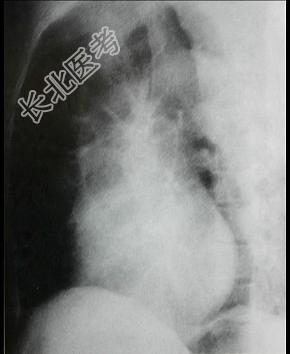

- 单项选择题对如下心脏左侧位片描述正确的是 ( )

A、左心室增大

B、左心房Ⅱ度增大

C、右心室增大

D、正常心脏

E、以上均错